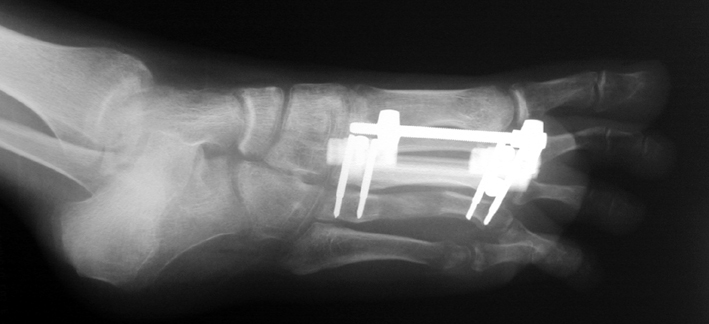

Surgical treatment may be required for metacarpal shortness because of cosmetic disturbance and fatigue in the dominant hand; and for metatarsal shortness because of cosmetic appearance, metatarsalgia, deformity due to dorsal shift of the short finger, pain and pressure ulcers due to plantar shift of the short finger, or difficulty in shoe wearing. Various techniques have been defined for the treatment of congenital metacarpal or metatarsal shortness. However, the most frequently used methods are acute lengthening with grafting, and distraction osteogenesis (callotasis). Callotasis method is preferred for lengthening more than 1 cm. In our department, we prefer distraction osteogenesis with unilateral or circular external fixator for lengthening of metacarpal and metatarsal bones.